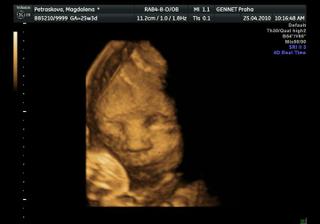

25.4.2010-razíme na 4D utz tak snad se nám princezna ukáže v plné kráse =0*

no vypadaj fakt velký =D